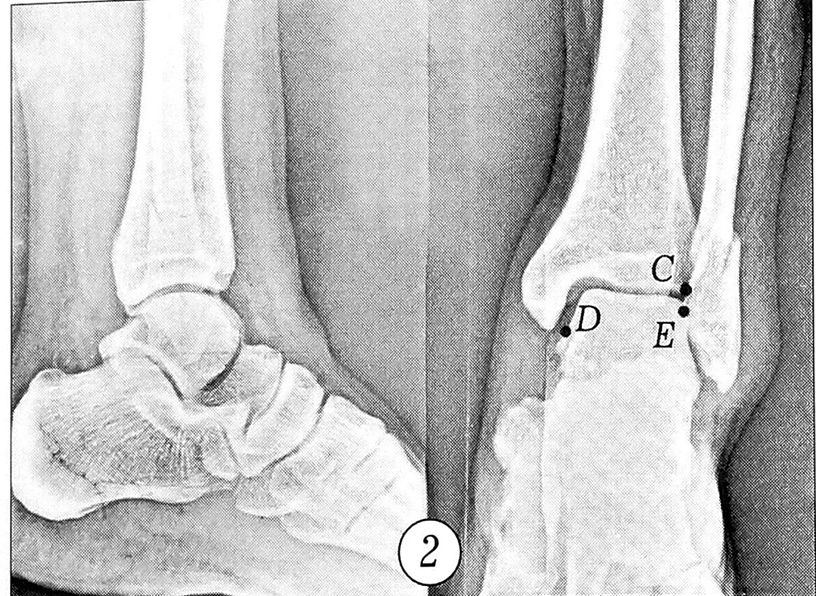

Рис. 2. Рентгенограммы левого голеностопного сустава больного Ц. с обозначенными параметрами (точки С, D, Е) на снимке в прямой проекции.

Больной Ц., 51 года, поступил в экстренном порядке с диагнозом: закрытый перелом наружной лодыжки слева, подвывих стопы кнаружи. Сделаны рентгенограммы левого голеностопного сустава в прямой и боковой проекциях (рис. 2). Выбраны и обозначены на прямой рентгенограмме следующие рентгенометрические параметры (точки): С — точка сопряжения суставной поверхности большеберцовой кости и наружной лодыжки (характеризует степень повреждения дистального межберцового синдесмоза); D — точка суставной поверхности таранной кости, расположенная на линии, соединяющей центр сустава (центр шарнира) с нижней точкой внутренней лодыжки (характеризует степень подвывиха стопы); Е — точка сопряжения суставной поверхности таранной кости и наружной лодыжки (характеризует степень смещения наружной лодыжки) (см. рис. 2). Описанным выше способом на рентгенограмму голеностопного сустава наложено измерительное устройство (выбран радиус R2), определены полярные координаты точек С, D, Е. Для левого (поврежденного) сустава координаты оказались следующими: точка С (рис. 3, а): осС = 35°, рС = 1,1; точка D (рис. 3, б): ocD = 70°, pD = 0,9; точка Е (рис. 3, в): <хЕ = 45°, рЕ = 0,8.